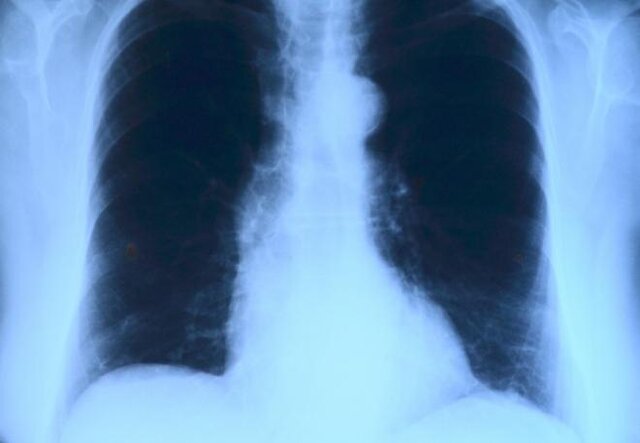

به گزارشامروله، در حال حاضر مردم جهان با شیوع کروناویروس مواجه هستند. این ویروس موجب بیماری کووید-۱۹ میشود، بیماری که عامل مشکلات تنفسی و آسیب دیدن ریه است. کروناویروس جدید تهدید بزرگی برای افرادی است که از سیستم ایمنی قوی برخوردار نیستند. همچنین افرادی که دچار مشکلات ریوی هستند بیشتر احتمال دارد به این ویروس آلوده شوند.

در این شرایط آگاهی از نشانههای هشداردهنده بیماری ریوی اهمیت بیشتری پیدا میکند. بسیاری از افراد دچار مشکلات تنفسی شده و تنها آن را بخشی از فرایند افزایش سن تلقی میکنند. هرچند، این وضعیت میتواند نشانه اولیه بیماری ریوی باشد. تشخیص به موقع این نشانه هشداردهنده میتواند در فرایند درمان مفید باشد.